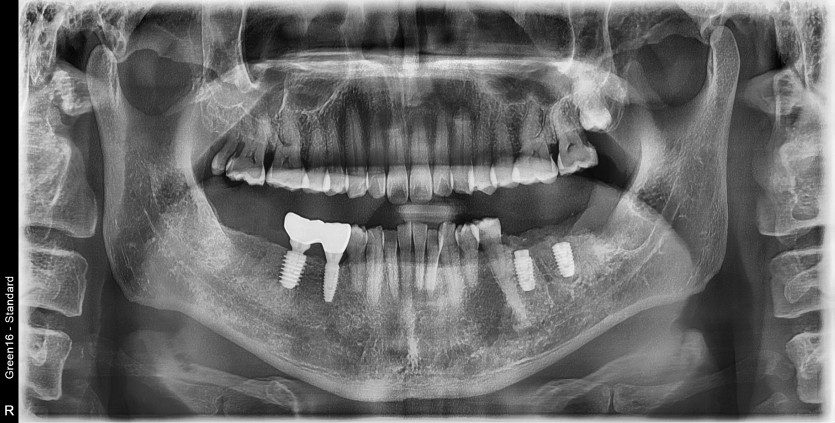

#38 사랑니 발치

구강 외과 전문의가 당일 발치했습니다.